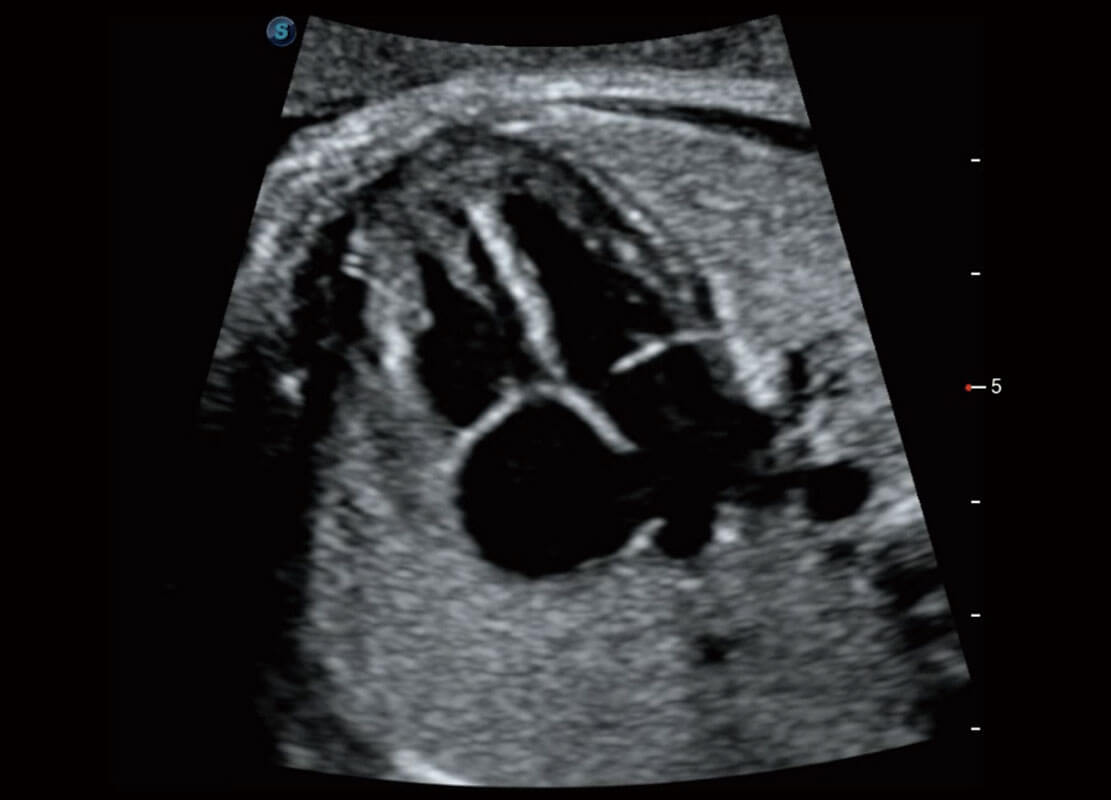

腔内妇科-卵巢

腔内三维-宫内节育器

腔内三维-光影成像